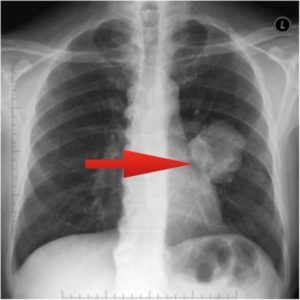

Расшифровка цифровых кодов флюорографии с примерами

02 - Затемнение в легочной ткани (инфильтрация,ателектаз, округлая тень, среднедолевой синдром и др.).

01 - Кольцевидная тень (полость).

Примечания:

При сочетании нескольких из перечисленных изменений каждое из них отмечается соответствующим кодом в каждой графоклетке.

Локализация, протяженность изменений отмечается дробью по второй графоклетке 1; 2; 3; 4; в числителе - правое легкое, в знаменателе - левое легкое (по полям).

Номер шифра легочных полей: 1 - первое, 2 - второе, 3 - третье, 4 - первое и второе, 5 - первое и третье, 6 - второе и третье, 7 - первое, второе и третье.